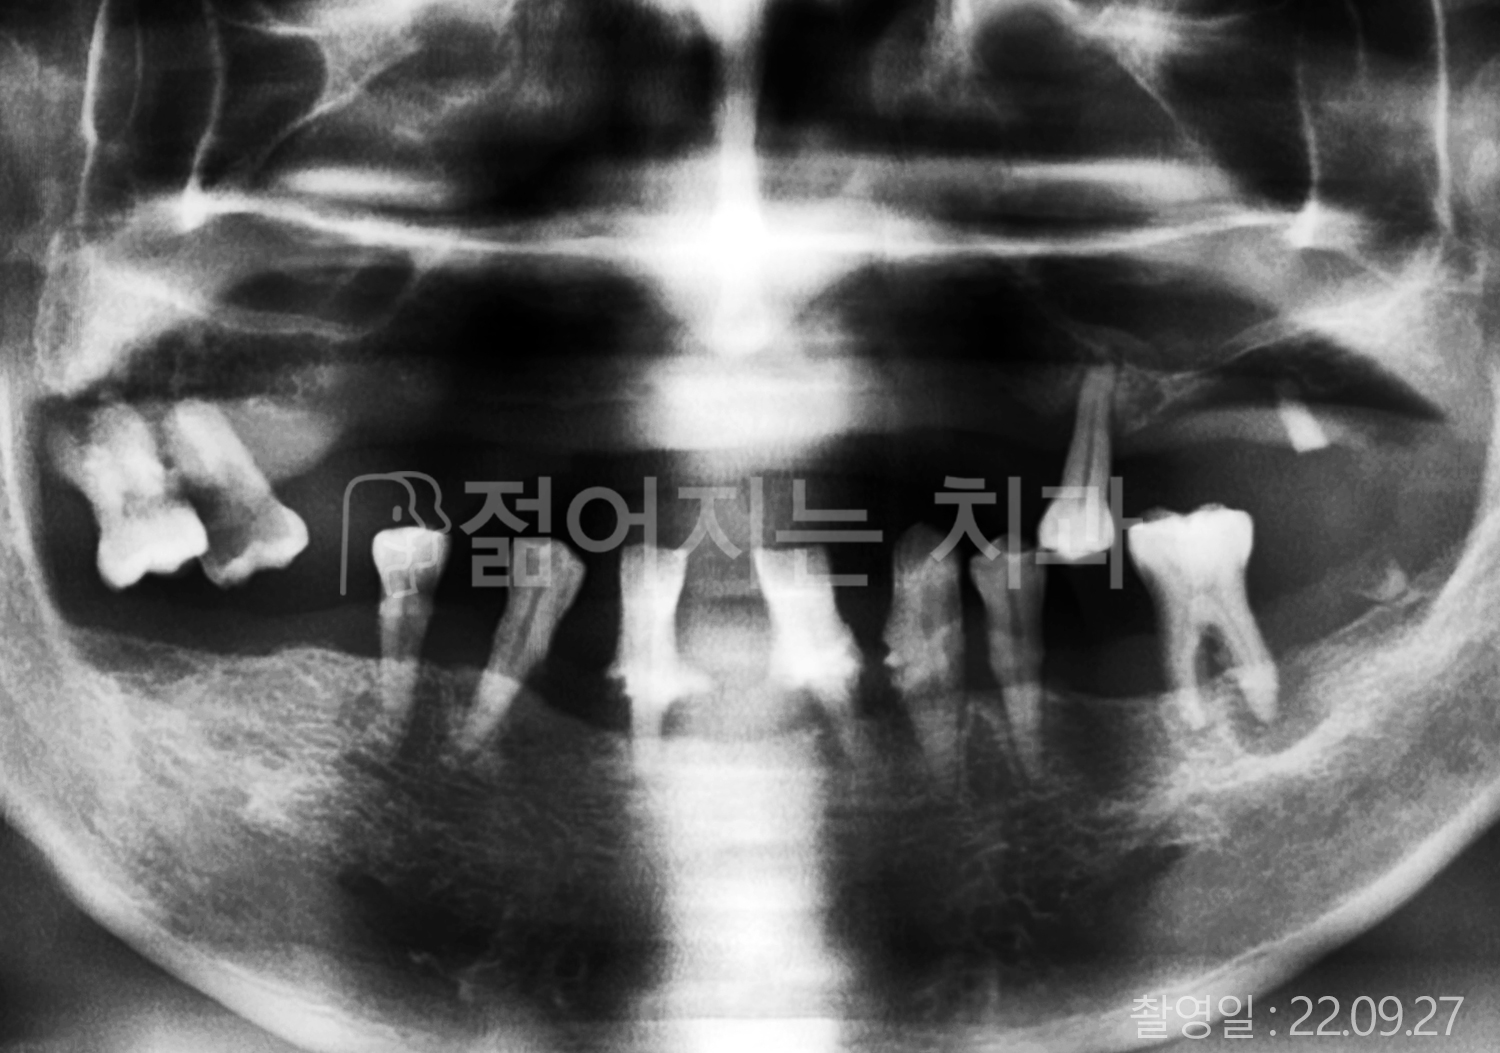

• 40대 전체치아 10개 이상 임플란트

• 70대 당뇨 전체치아 10개 이상 임플란트

• 60대 전체치아 10개 이상 임플란트

• 60대 고혈압, 당뇨, 고지혈증 전체치아 10개 이상 임플란트

• 50대 전체치아 10개 이상 임플란트

• 70대 고혈압, 당뇨 전체치아 10개 이상 임플란트

• 60대 고혈압 전체치아 10개 이상 임플란트

• 50대 고혈압, 당뇨, 고지혈증 전체치아 10개 이상 임플란트

• 60대 고혈압, 고지혈증 전체치아 10개 이상 임플란트